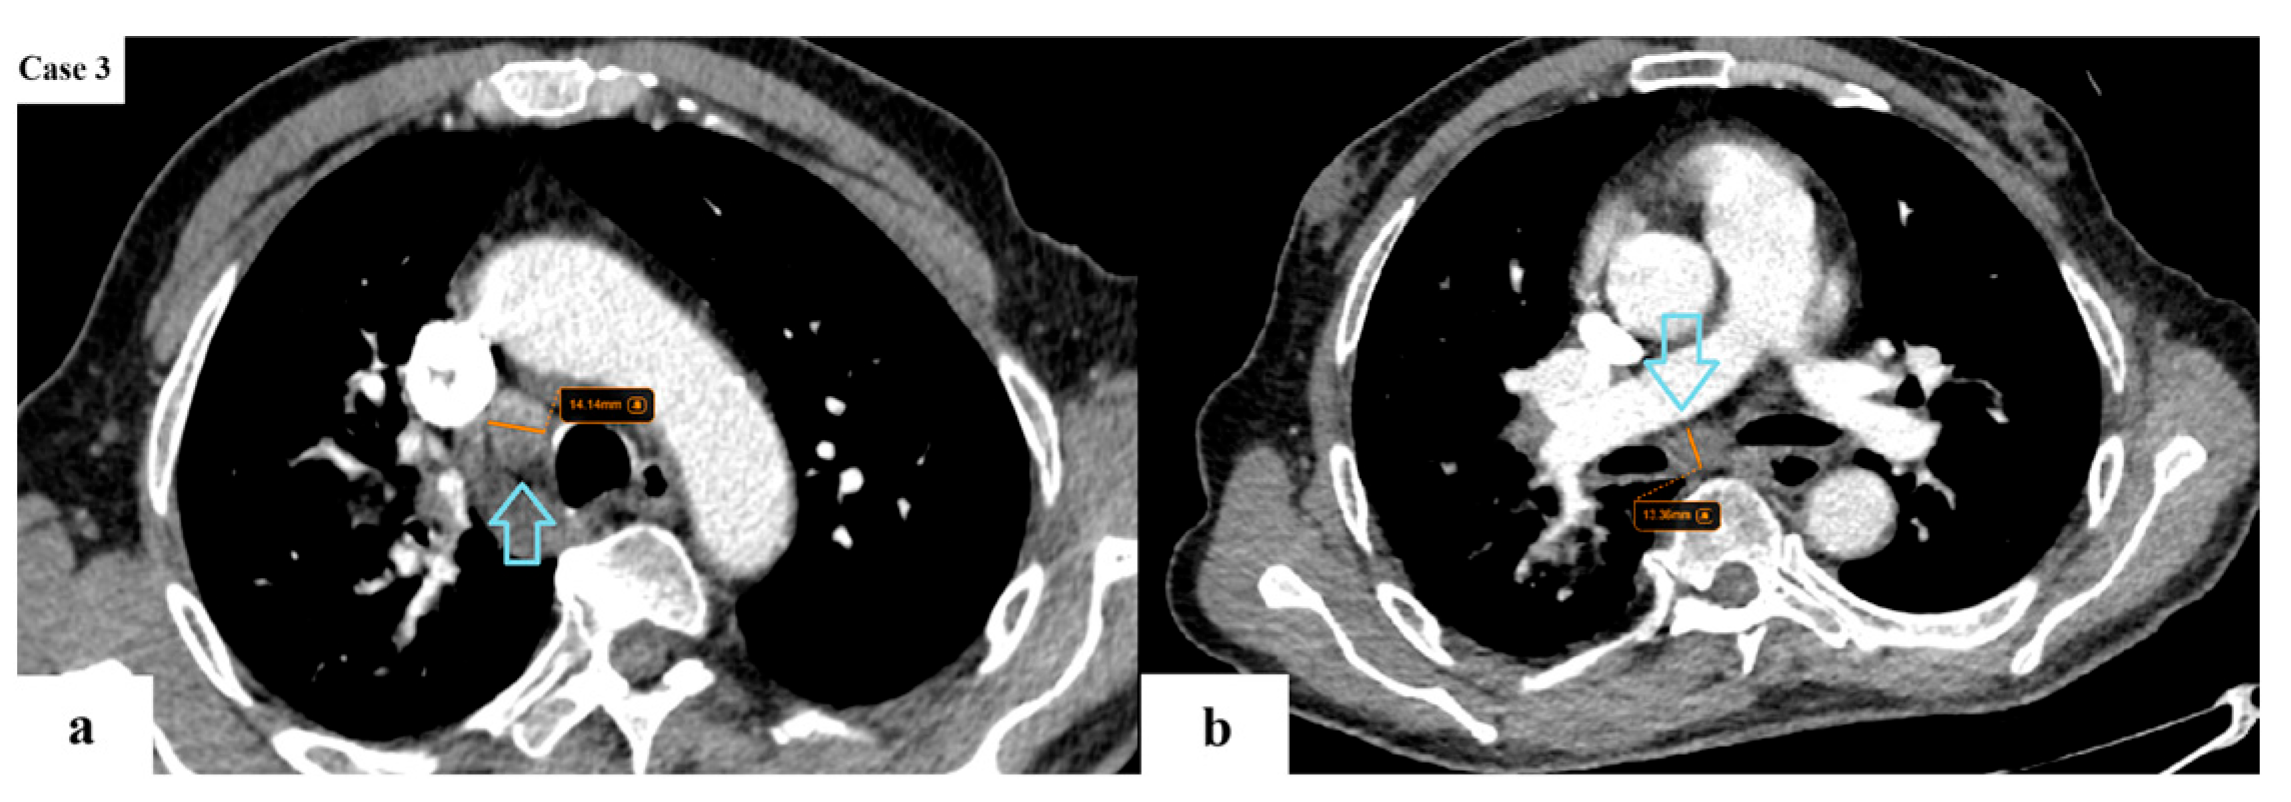

- N descriptor: subdivision of N2 disease into single-station (N2a) and multi-station (N2b);

| Imaging features | Spiculated margins: 88% Central necrosis: 38.4% Cavity: 10.4% Lymphangitic spread: 43.2% |